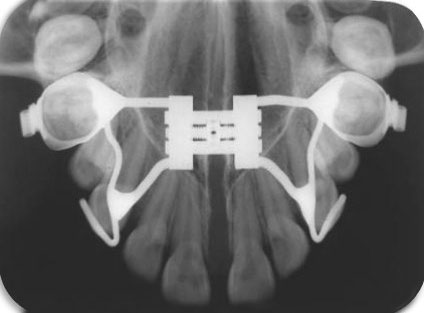

Localización de piezas dentarias